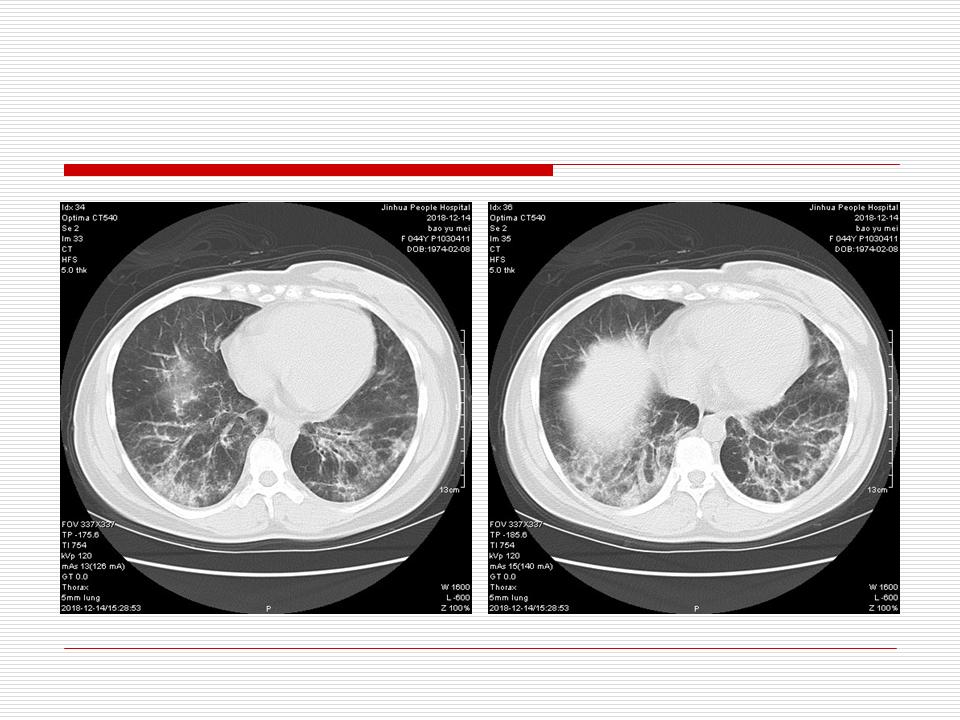

肺部阴影永恒且最重需要鉴别的是:到底是炎症还是肿瘤?但临床的病例中的影像表现难以界定或有些肿瘤特征,同时又有些炎症特点是非常常见的情况。作为临床医生我们怎么去总结分析,并找到之所以是炎症或之所以是肿瘤的细微差别或特点非常重要,也非常有用。2019.12.7浙江省2019年胸心外科学学术年会在宁波召开时,我的临床病例分析与经验总结<那些像肺癌的炎症与像炎症的肺癌>获得在大会交流的机会,以下为该PPT的内容,与你分享,希望对同道有益,有借鉴与启迪。若有探讨与进一不完善的建议,欢迎文末留言讨论: